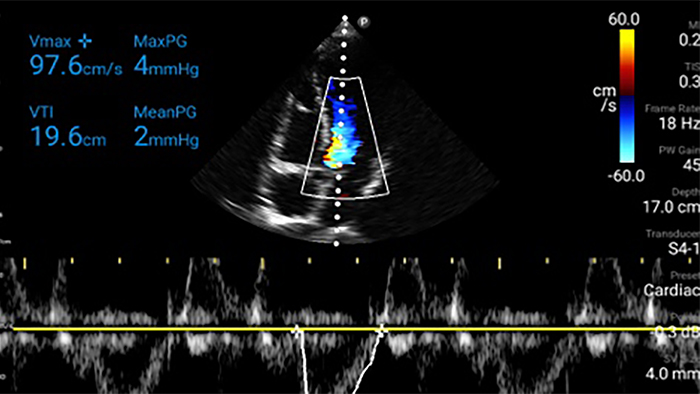

Every second counts in cardiac care

Heart attack patients need immediate care. Lumify's cardiac presets can help patients get diagnosed faster to improve their outcomes.

Lumify S4-1 broadband phased array transducer

• 4 to 1 MHz extended operating frequency range • 2D, color Doppler, M-mode, advanced XRES and multivariate harmonic imaging • High-resolution imaging for abdominal and cardiac applications: Cardiac, OB/GYN, Lung, Abdomen and FAST imaging preset optimizations Lumify aids life-saving technology in prehospital setting